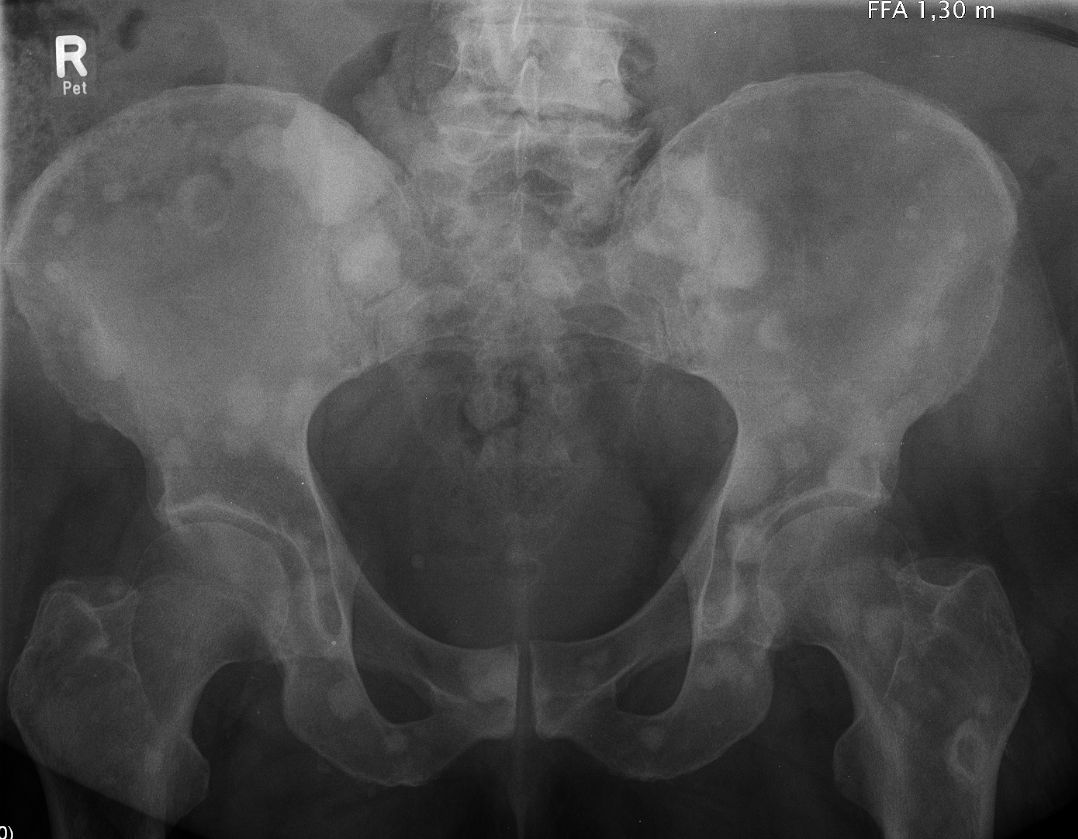

Becken |

68-jähriger Mann mitprimär metastasiertem

Prostatakarzinom cT4 cN1 M1b. Gleason 8, PSA 254. LHRH-Analoga und Chemotherapie

seit 3 Monaten. Typische osteoplastihsche Metastasen ohne Beschwerden.![]() | ||||||||||||||||||||